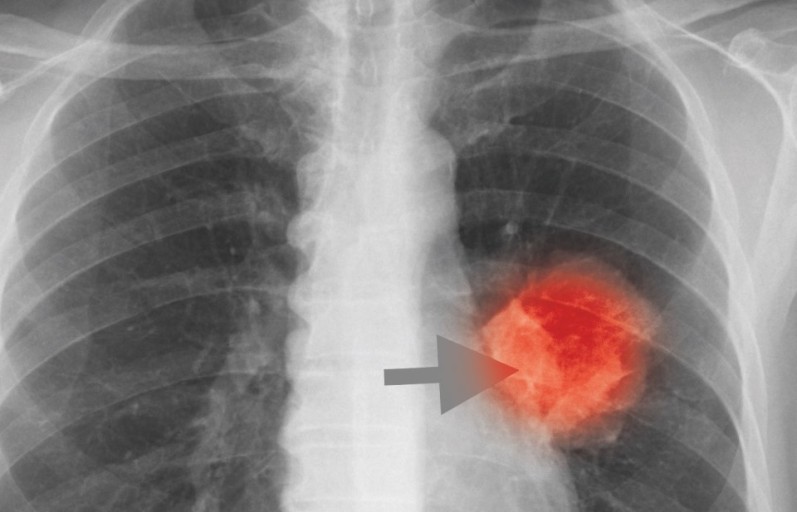

폐암은 위암, 갑상선암 다음으로 3번째로 발병 빈도가 높은 3대 암 중 한 가지입니다. 폐암은 재발과 전이까지의 빈도도 잦은지라 완치가 어렵다고 하며 폐암 발병 초기에는 거의 증상이 없을 수가 있어 수술이 불가능한 3기, 혹은 4기에 주로 진단된다고 합니다.

폐암 4기에 이르게 되면 5년 생존률이 30% 대로 떨어지게 된다고 합니다. 그리해서 폐암은 암 질병이자 중 사망자 비율이 가장 높은 것으로 나타나고 있습니다.